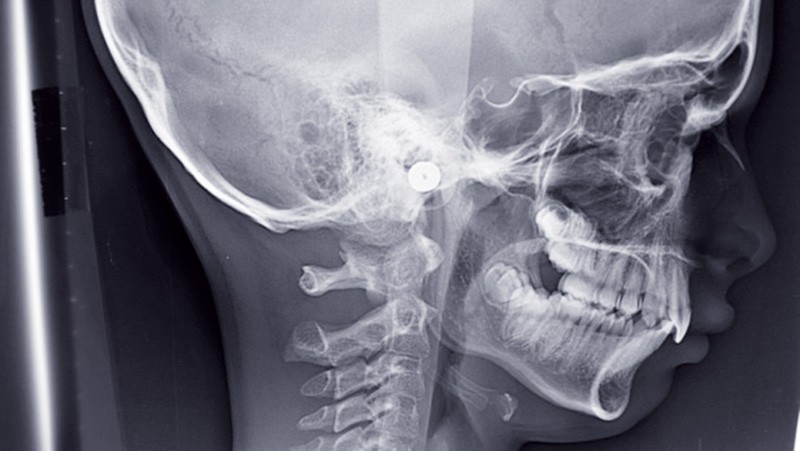

Les Voies Aériennes Supérieures (VAS), dédiées à la respiration, la déglutition et la phonation s’étendent des fosses nasales à la trachée extra- thoracique. Seul le pharynx, structure molle sans armature osseuse ou cartilagineuse permettant de maintenir l’ouverture pour la respiration, est concerné par le SAOS. L’obstruction siège en arrière du voile du palais, au niveau de la base de la langue et de l’hypopharynx. Une rétrusion maxillaire, mandibulaire ou maxillo- mandibulaire, un palais dur étroit, un os hyoïde bas, l’épaississement du palais mou, de la langue, des parois latérales, un voile du palais allongé, une luette élargie, sont les éléments contribuant à la réduction des VAS. L’hypertrophie amygdalienne et des végétations, l’obésité sont aussi une cause…